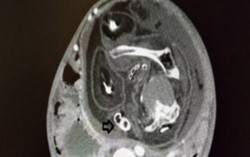

Bụng bé trai 4 tháng tuổi phình to vì hiện tượng ‘thai trong thai’

Phòng & chữa bệnh 19:29 08/01/2019Các bác sĩ Bệnh viện Nhi đồng 2 (TPHCM) vừa phẫu thuật lấy khối u thai hiếm gặp trong bụng bé trai 4 tháng tuổi.